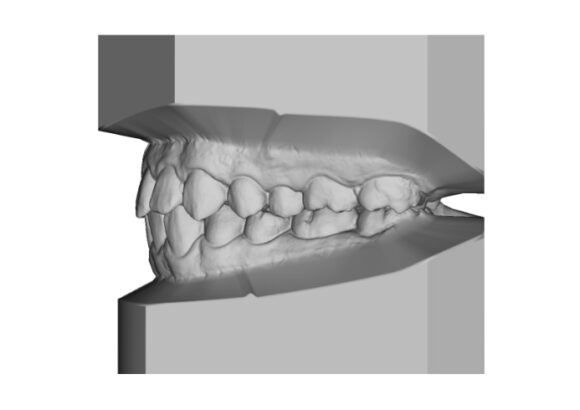

El escaneo dental es un dispositivo digital utilizado para capturar impresiones tridimensionales de la boca del paciente.

Este tipo de escaneo permite recrear la dentadura con una precisión que supera con mucho las muestras tomadas con materiales de impresión tradicionales.

• Réplica exacta de las estructuras dentales y tejidos adyacentes del paciente.

• Los escaneos son considerados tan precisos si no más exacto que los moldes de yeso. El proceso de escaneo es más cómodo para pacientes especialmente con reflejo nauseoso.

• Mayor precisión comparado con modelos convencionales de alginato, sin necesidad de repetir la toma de impresión.

• Comodidad para pacientes con reflejos de nauseas.